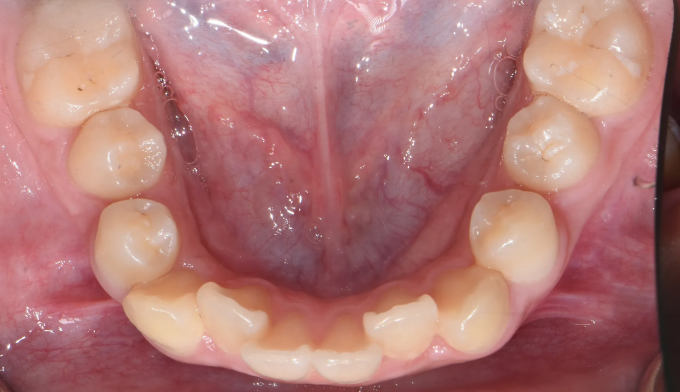

앞니불규칙

Before

After